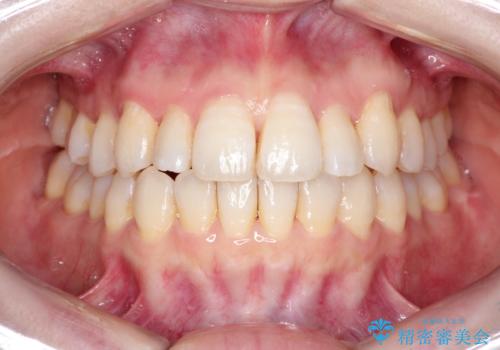

インビザラインで八重歯の矯正

使用時間を守っていただけたので、比較的スムーズに矯正を終了することができました。